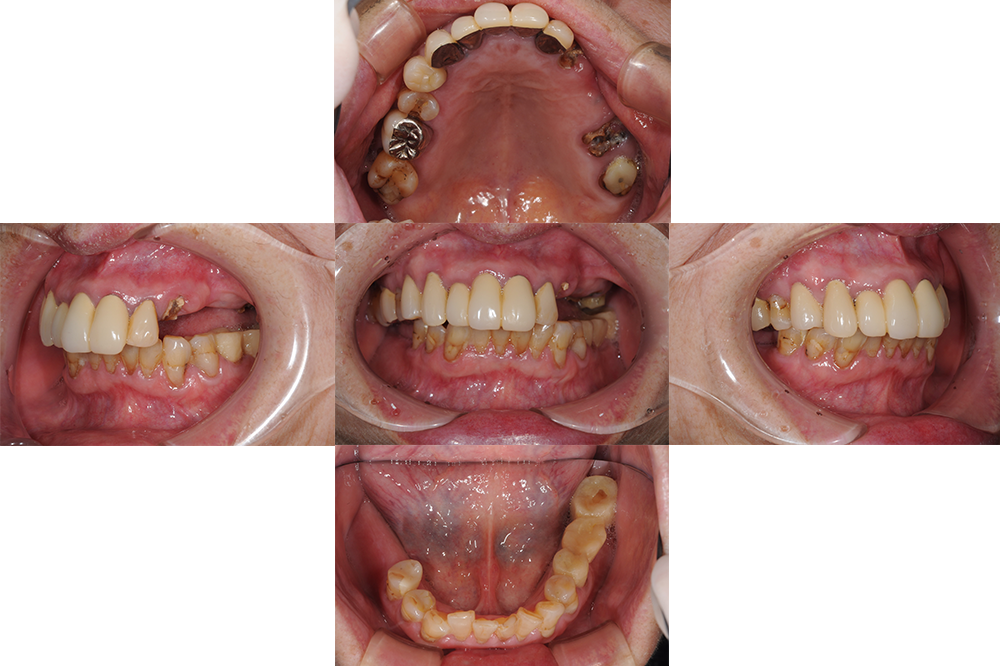

主訴 奥歯が外れた

治療経過 高齢ではあったが、入れ歯はどうしてもいれたくないということでインプラントを選択。

上顎は長期的な予後が見込める歯が少なく多数のインプラントを必要としたが、一時的にも義歯を使うことなく、咬める場所を温存しながらインプラントへと移行できた。

初診時不安定だった咬み合わせもスムーズに行えるようになり、不安なく食事ができるお口の状態を獲得できた。